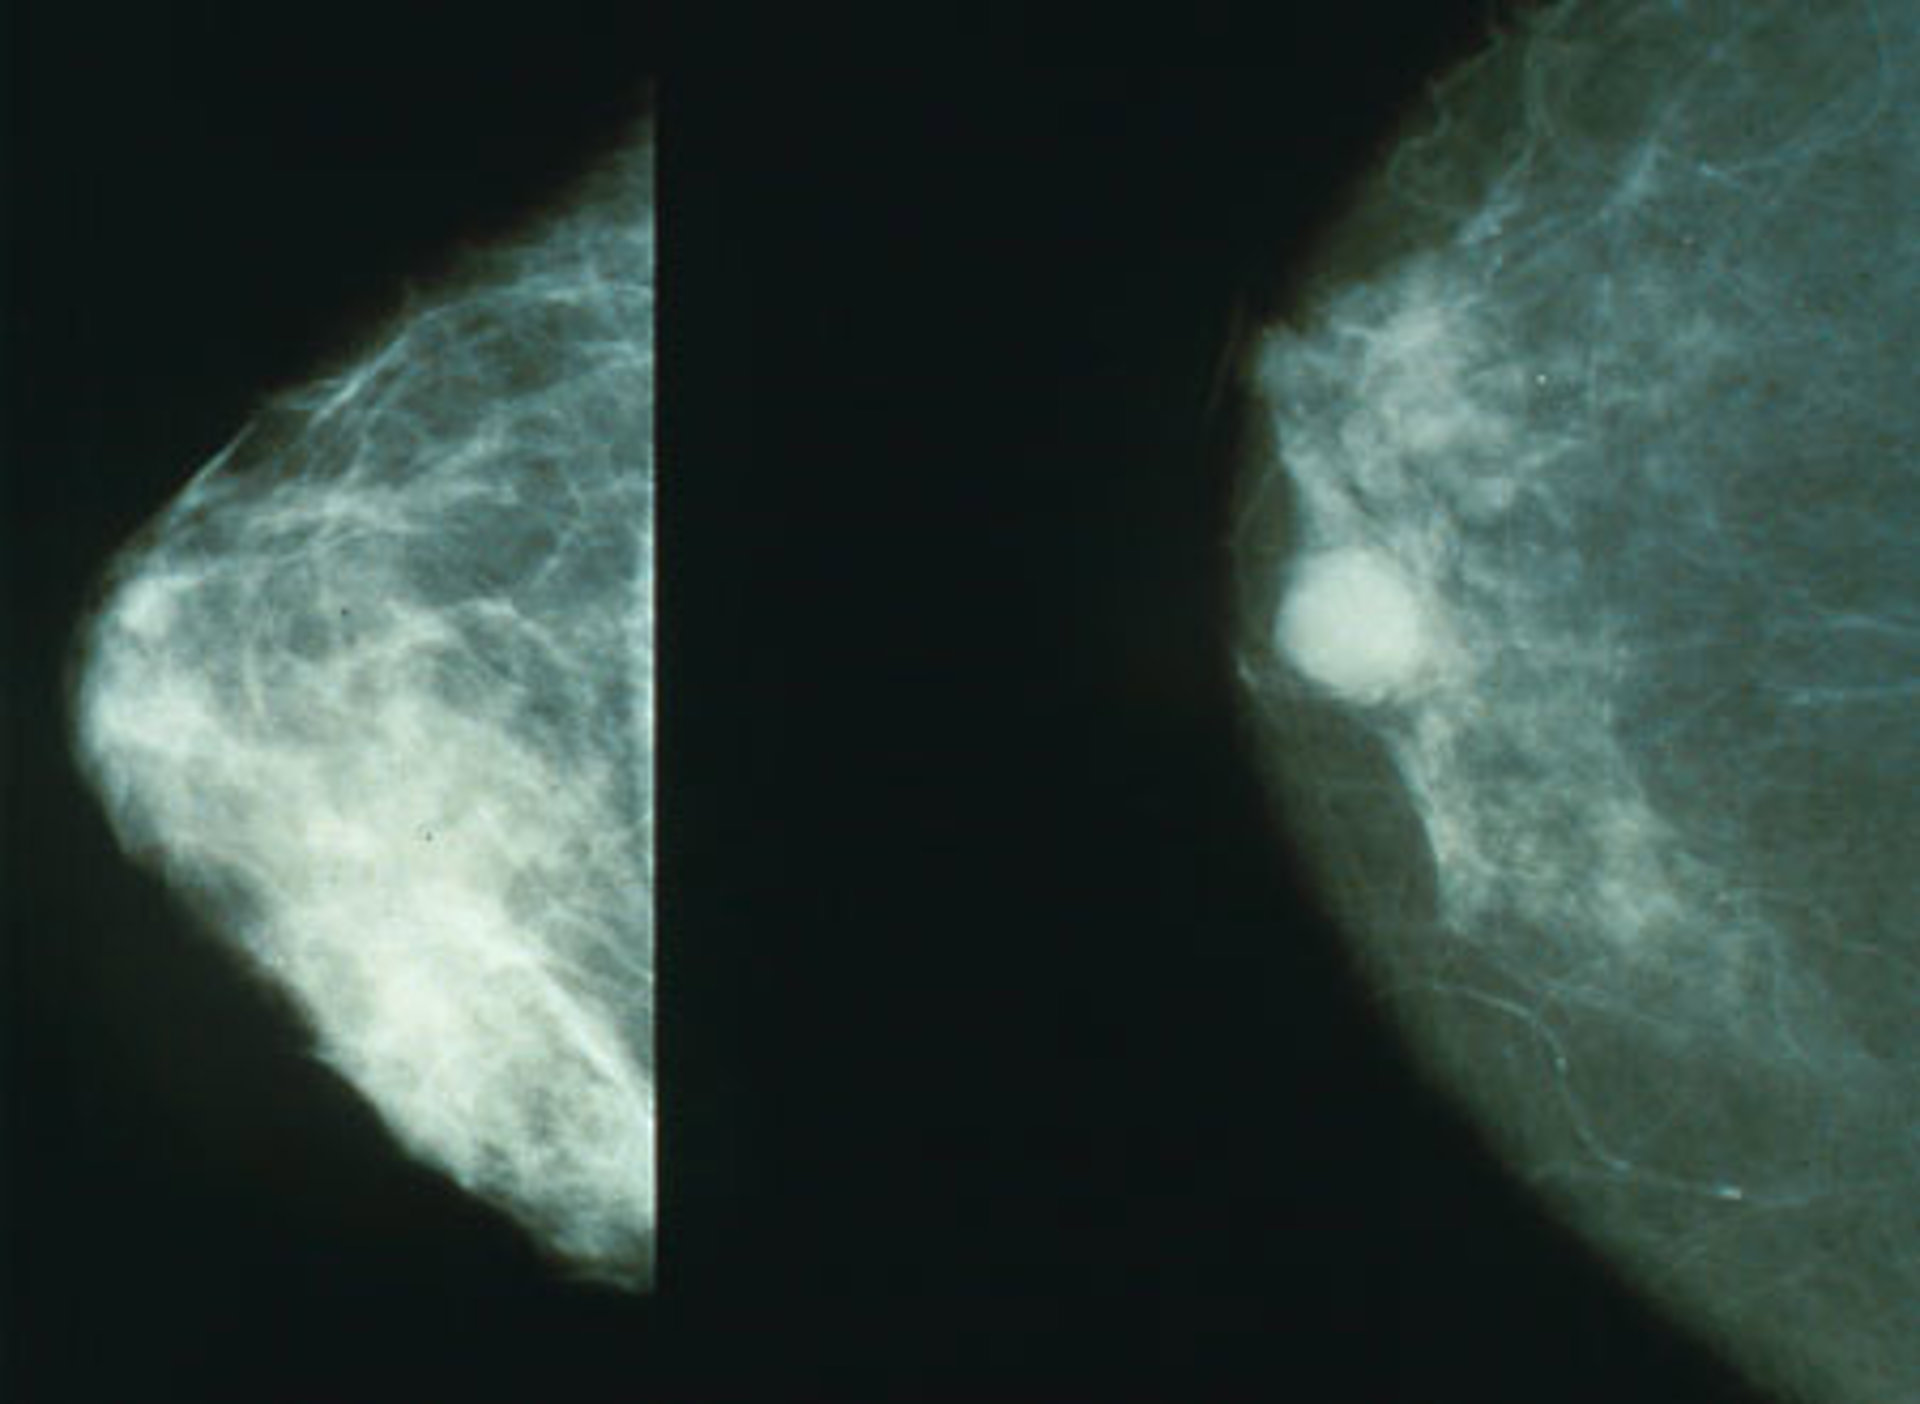

El porcentaje de mujeres con cáncer de mama que sufre una recidiva ha descendido hasta llegar al 25 por ciento en los últimos años, gracias a los nuevos tratamientos disponibles y a las campañas de cribado puestas en marcha por las autoridades sanitarias, según han concluido los oncólogos reunidos estos días en Roma (Italia) en un simposio organizado por AstraZeneca.

"El índice de recaídas ha descendido, no obstante, se están realizando diversos estudios de biología molecular para conocer por qué estas pacientes que primeramente responden bien, luego más tarde se vuelven resistentes", ha explicado la jefa del Servicio de Hematología y Oncología Médica del Hospital Clínico de Valencia, la doctora Ana Lluch.

En cuanto a las nuevas dianas terapéuticas, "el 70 por ciento de los tumores de mama son hormonodependientes, por lo que los tratamientos hormonales suponen un gran avance, ya que poseen una gran eficacia y no añaden toxicidad", apunta esta experta.